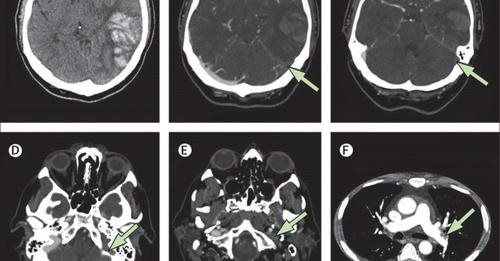

Biểu hiện huyết khối trên phim chụp.

CVST liên quan đến VITT có tỷ lệ tử vong rất cao. Ngay cả khi không có VITT, CVST là một tình trạng bệnh lý nghiêm trọng, với khoảng 4% bệnh nhân tử vong khi nhập viện. Tuy nhiên, ở những bệnh nhân có CVST liên quan đến VITT được quan sát trong nghiên cứu này, tỷ lệ tử vong khi nhập viện cao hơn khoảng 7 lần, ở mức 29%.